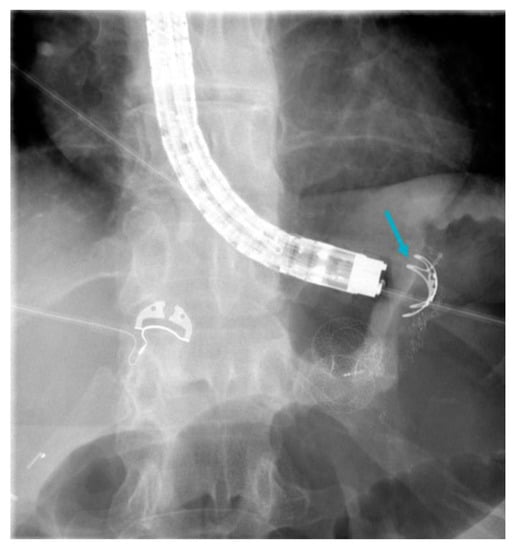

- Skidmore, A.P. Use of lumen-apposing metal stents (LAMS) in the management of gastro jejunostomy stricture following Roux-en-Y Gastric Bypass for obesity: A prospective series. BMC Surg. 2021, 21, 314. [Google Scholar] [CrossRef] [PubMed]

- Mansoor, M.S.; Tejada, J.; A Parsa, N.; Yoon, E.; Hida, S. Off label use of lumen-apposing metal stent for persistent gastro-jejunal anastomotic stricture. World J. Gastrointest. Endosc. 2018, 10, 117–120. [Google Scholar] [CrossRef]

- Uchima, H.; Abu-Suboh, M.; Mata, A.; Cruz, M.; Espinos, J. Lumen-apposing metal stent for the treatment of refractory gastrojejunal anastomotic stricture after laparoscopic gastric bypass. Gastrointest. Endosc. 2016, 83, 251. [Google Scholar] [CrossRef] [PubMed]